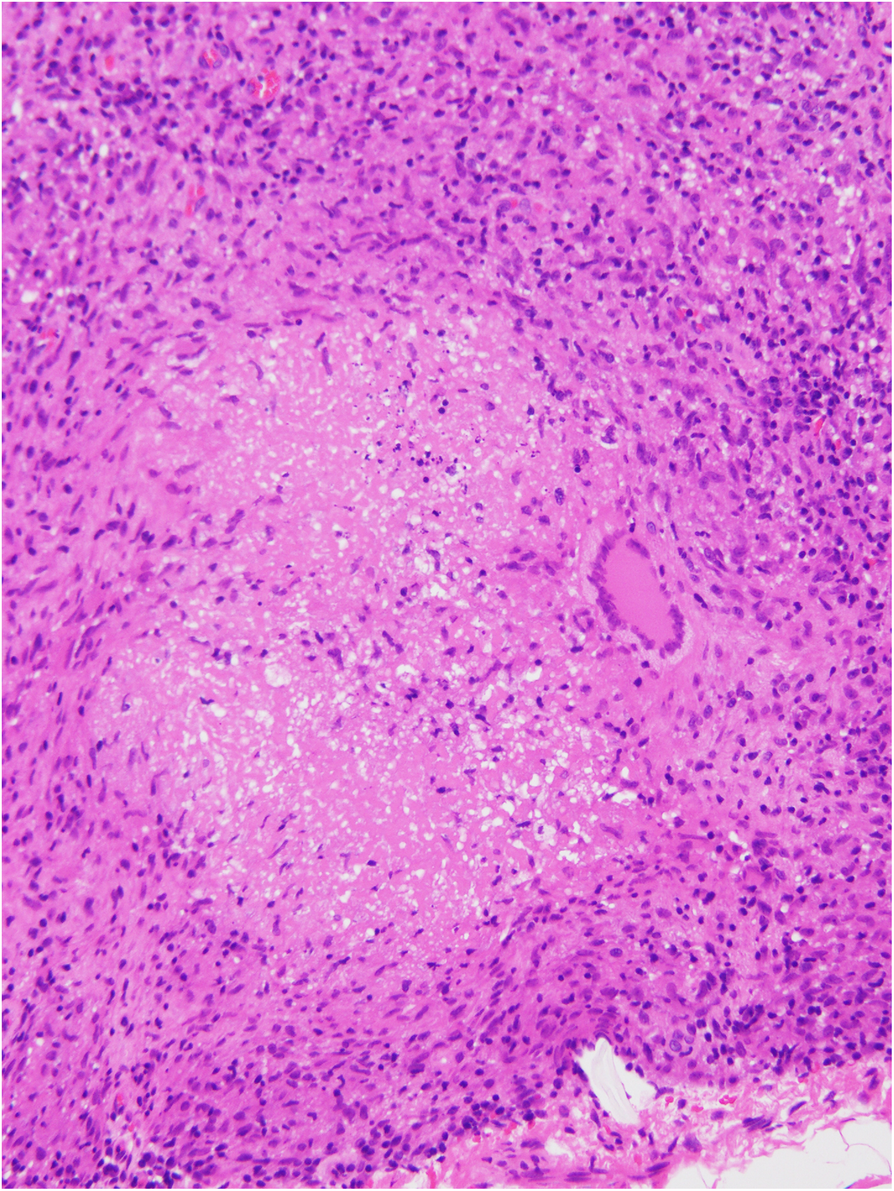

Fig. 3From: Improvement of multiple intraperitoneal nodules resembling peritoneal cancer that developed after peritoneal dialysis-related peritonitis caused by Mycobacterium abscessus with literature review: granuloma or carcinomaThe result of biopsy from the lesion around the external cuffBack to article page